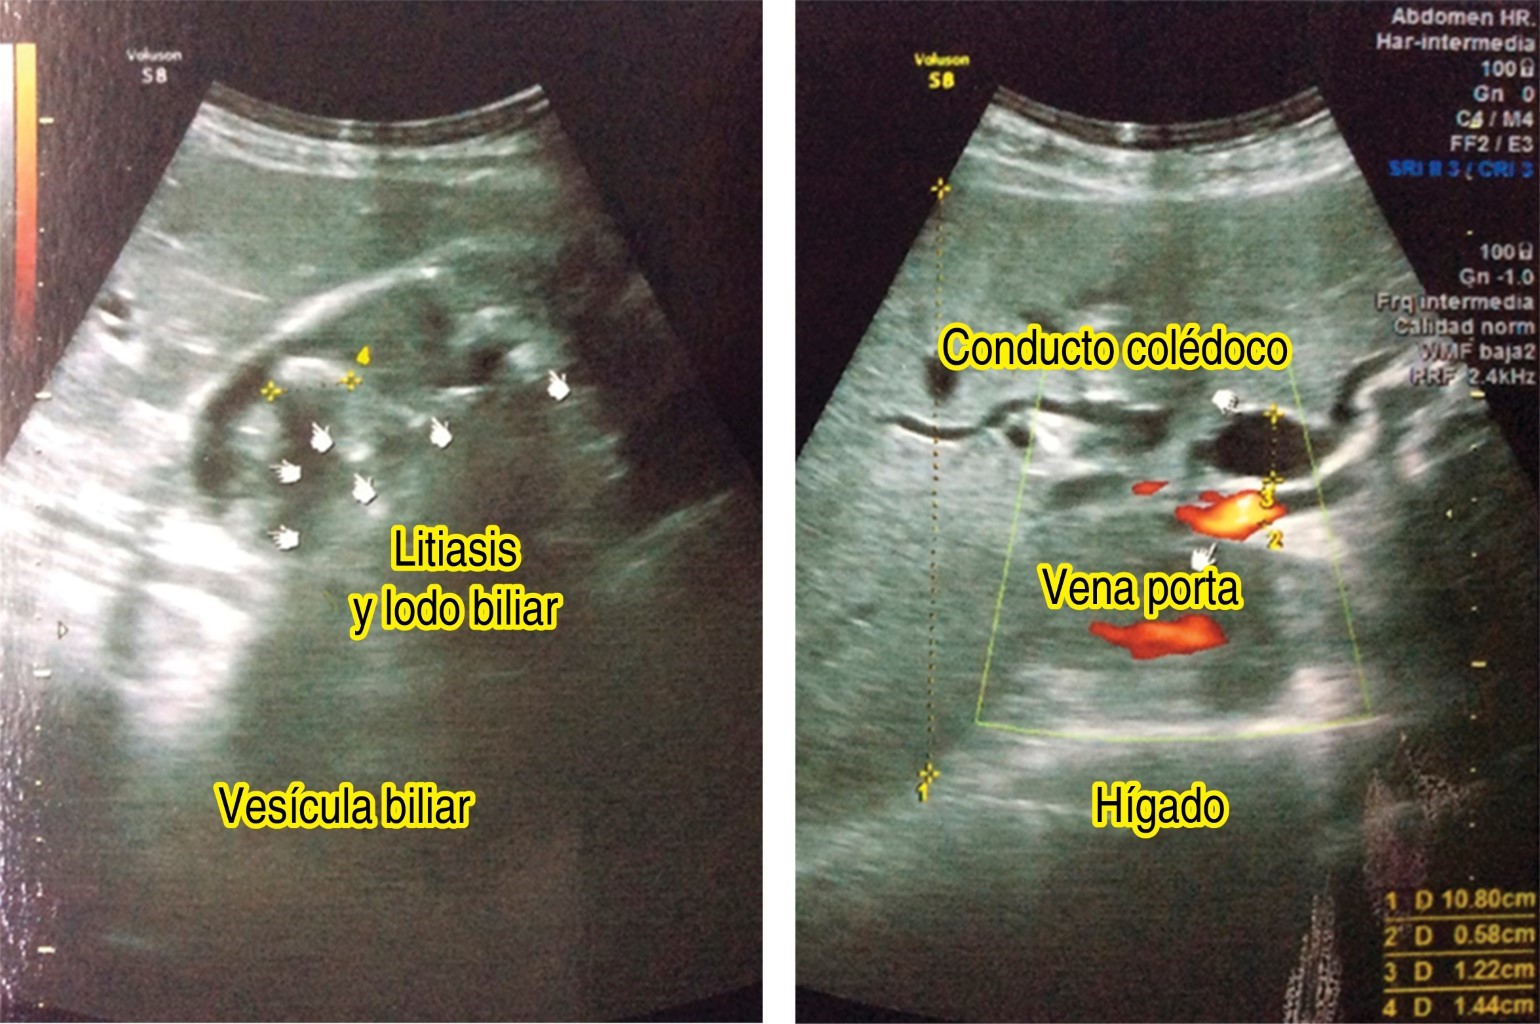

El ultrasonido abdominal realizado con anterioridad reporta (Figura 1): "dilatación de los conductos hepáticos y biliares. Vesícula biliar con múltiples litos, así como barro biliar. Colédoco: de 12 mm de diámetro (normal hasta 4 mm), no logra identificarse proceso obstructivo (lito). Conclusión: datos compatibles con colelitiasis con coledocolitiasis y colangitis asociado."

Figura 1